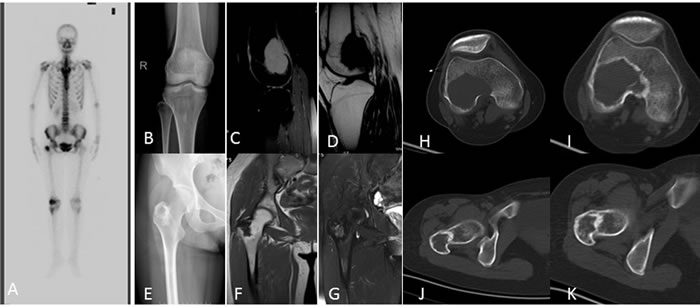

Figure 4: A 27-year-old woman with right knee pain A. Bone scintigraphy showed a diffuse increased radionuclide uptake in the greater trochanter of femur, and a peripherally increased uptake and photopenia centrally in the distal femur. B. Anteroposterior radiograph of the knee shows a well-circumstanced osteolytic lesion with a narrow zone of transition. C., D. MRI shows a well-defined lesion with T2/T1 homogeneous intermediate and hyperintensity. E. Antero-posterior radiograph of the pelvic shows an osteolytic lesion with a sclerotic ring margin in the greater trochanter of the femur. F., G. MRI shows an irregular lesion with T1 low signal intensity and T2 heterogeneous hyperintensity. H., I. CT shows ring-like sclerosis around the outer margin after four months of treatment with denosumab. J., K. CT shows increased sclerosis in the center of the lesion.

On radiographs (n = 14), 16 lesions manifested as geographic lucent lesions, and 1 lesion showed soft tissue density with stripe-like calcification (Figure 2B). Among these lesions, 9 lesions showed ring-like sclerosis (Figure 3B), 3 lesions showed patchy sclerosis (Figure 4E), and 4 lesions showed narrow transition without sclerosis (Figure 4B). Based on Campanacci et al’s grading system[23], 5 lesions were classified as grade III, 10 lesions as grade II, and 1 lesion as grade I. One lesion located in the calcaneus was treated with denosumab after one year, and a radiograph demonstrated shrinkage of the osteolytic zone and the formation of sclerosis in the center of the lesion and adjoining bone cortex (Figure 1D-1E). Four lesions showed increased sclerosis in the center and outer margin after six months.

On CT scanning (n = 13), 13 lesions showed marrow replacement by tissue with homogeneous attenuation, with homogeneity in 1 lesion. Nine lesions more clearly demonstrated sclerotic margins or patchy sclerosis (Figure 1A-1B). Three lesions showed a narrow transition without sclerosis. Eight lesions showed cortical discontinuity, and 5 lesions showed soft tissue mass throughout the bone cortex. Two lesions were treated with denosumab after four months; CT showed ring-like sclerosis around the outer margin (Figure 4H-4I) and increased sclerosis in the center of the lesion (Figure 4J-4K).

On MRI (n = 8), 2 lesions showed marrow replacement by homogeneous tissue, and 6 lesions showed marrow replacement by heterogeneous tissue on T1-weighted images. Two lesions had intermediate signal intensity (similar to that of the muscle), and 3 lesions showed predominately intermediate signal intensity with patchy or stripe-like low signal intensify (Figure 5C); 2 lesions showed mildly higher intensity than muscle, and 1 lesion showed low signal intensity on T1-weighted MR images (Figure 4F). On T2-weighted MR images, the signal intensity was heterogeneous in 6 lesions and homogeneous in 2 lesions. Five lesions showed predominately high signal intensity (similar to that of fat) with patchy or stripe-like low signal intensity (Figure 5D), and 1 lesion showed higher signal intensity than that of fat; 2 lesions showed homogeneous high signal intensity (Figure 4C). One lesion subjected to contrast enhancement showed obvious enhancement. In addition, cortical destruction with an associated soft tissue mass and extensive edema was seen 3 lesions.

Bone scintigraphy (n = 1) showed a diffuse increased radionuclide uptake in the greater trochanter of femur, and a peripherally increased uptake and photopenia centrally in the distal femur (Figure 4A).